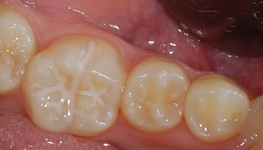

| ¾Õ´Ï ÃæÄ¡ |